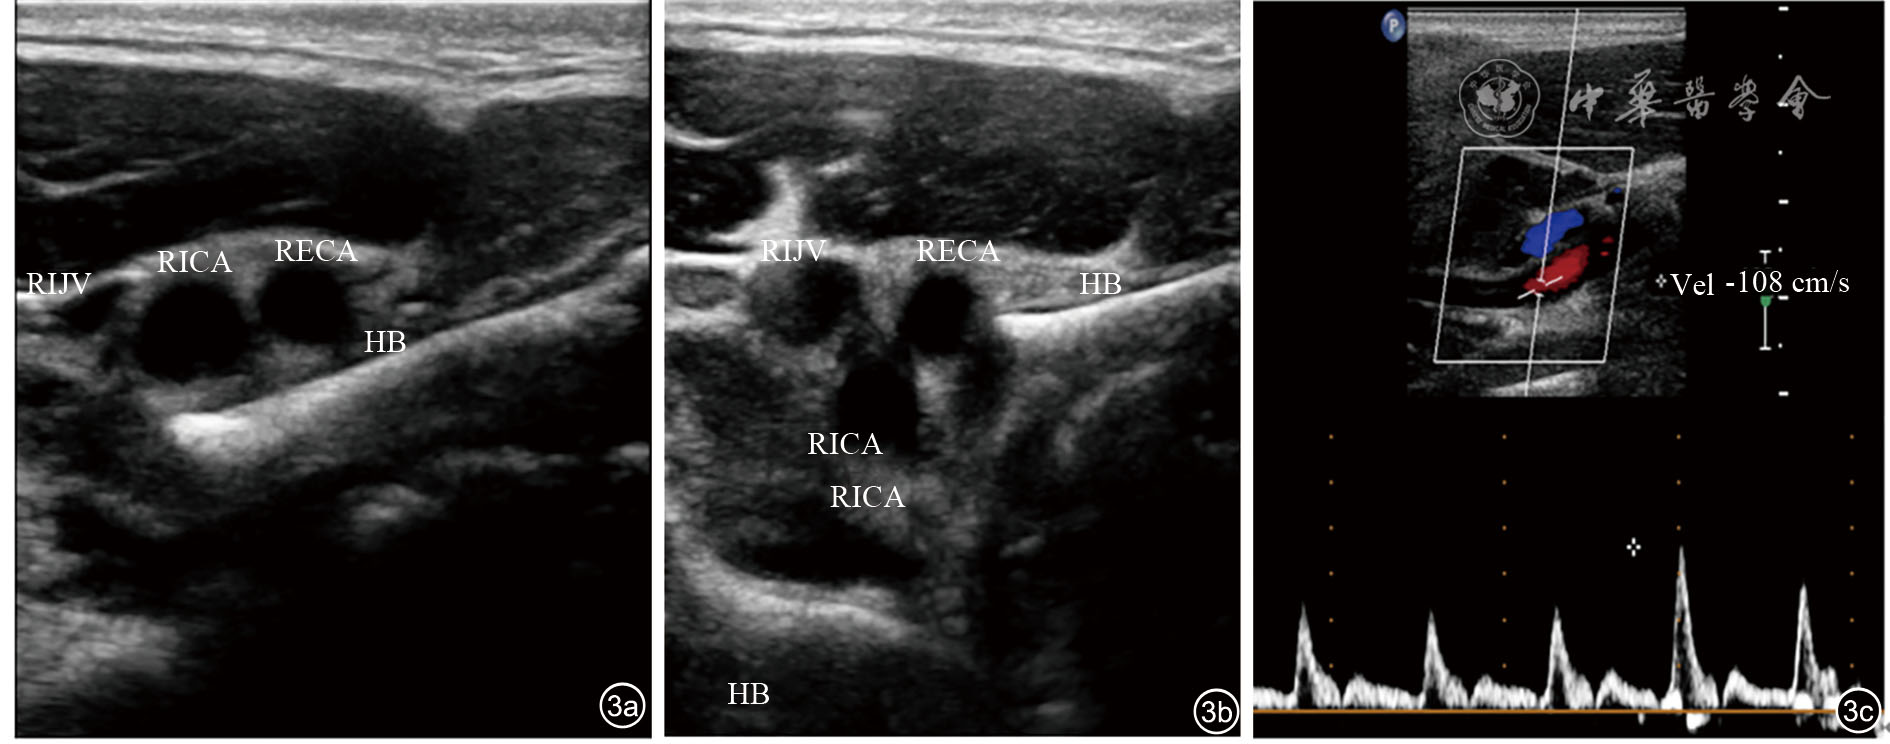

图3 舌骨颈动脉撞击综合征吞咽动作前后超声图像。图a为吞咽动作前;图b为吞咽动作后;图c示发生撞击后颈内动脉流速增快 注:RIJV为右侧颈内静脉;RICA为右侧颈内动脉;RECA为右侧颈外动脉;HB为舌骨

患者,男性,19岁,因再次发作左侧肢体无力1周,在当地县医院治疗后症状缓解不明显,于2021年4月20日再次来陆军特色医学中心复诊。患者2018年(16岁)出现行走不稳、视物旋转,在当地医院诊断为“耳石症”,复位后再未发作。于2020年11月无明显诱因,出现发作性左侧肢体无力、偏身触觉丧失1周,在当地某医院治疗后恢复出院。后于2021年1月、3月及4月再次发作左侧肢体无力。查体:左侧面部感觉较右侧减退,口角右歪,左侧肢体感觉较右侧减退,跟腱反射(++),美国国立卫生研究院卒中量表(National Institute of Health stroke scale,NIHSS)评分2分(面瘫1+感觉1)。头颅CT及头颈CT血管造影(2021年3月10日)显示:右侧大脑半球脑梗死后改变并多发软化灶形成(图1)。右侧大脑中动脉较对侧细小、分支稀疏;左侧胚胎型大脑后动脉,右侧后交通动脉开放。再次分析患者CT血管造影图像,发现患者颈椎存在侧弯畸形,右侧颈动脉分叉处位于右侧舌骨大角外下方,颈内外动脉与右侧舌骨大角紧邻,左侧颈动脉分叉处位于左侧舌骨大角内上方(图2)。临床医师建议完善动态超声检查。超声检查显示(2021年4月29日):(1)右侧颈内动脉斑块形成。(2)右侧舌骨大角随吞咽动作反复撞击颈内动脉,考虑:舌骨颈动脉撞击综合征(图3,动态图1)。患者于2021年6月在陆军特色医学中心行右侧舌骨大角部分切除术(图4)。术后规律服用抗凝药物,复查2次颈动脉超声,提示舌骨残端远离颈内动脉,颈内动脉斑块稳定,表现为低回声扁平斑,纤维帽完整(图5)。头颅CT显示颅内病灶较术前未见增多、范围未见增大(图6)。随访半年患者未再出现过左侧肢体无力等不适。